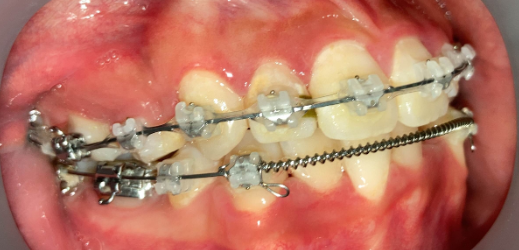

リカバリー症例の初診時の口腔内|奈良の矯正歯科

初診時

他院で非抜歯矯正を受けたものの、口元の突出感が改善せず来院。精密検査の結果、上下4本の抜歯が必要と判断し、ワイヤー矯正でやり直しました。